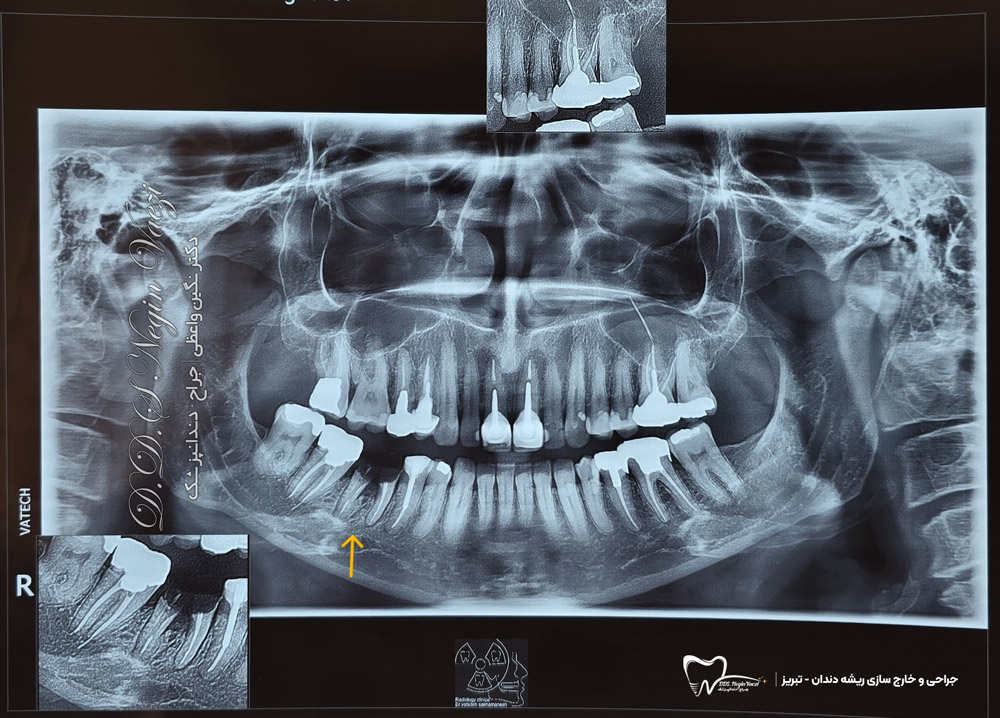

در عکس رادیوگرافی بالا، میتوانید وضعیت قبل از جراحی و محل ریشه های باقیمانده را مشاهده کنید. در این نمونه کار؛ جراحی خارج سازی ریشه های غیرقابل نگه داری دندان، انجام کورتاژ و شست و شوی کامل ساکت و انجام socket preservation (پیوند استخوان بلافاصله بعد از کشیدن دندان) جهت کاهش تحلیل استخوان و تامین حجم مناسب استخوان برای درمان ایمپلنت بعدی انجام شده است.